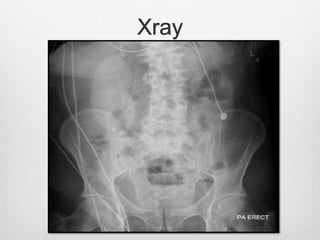

Xray

Case 2

Case 1  76year old man with h/o DM/ HTN  Presented to ED with epigastric painCT abdomen NAD  Baseline creatinine 80  Cardiogenic shockAMIsalvage angioplasty  A week later creatinine up to 750